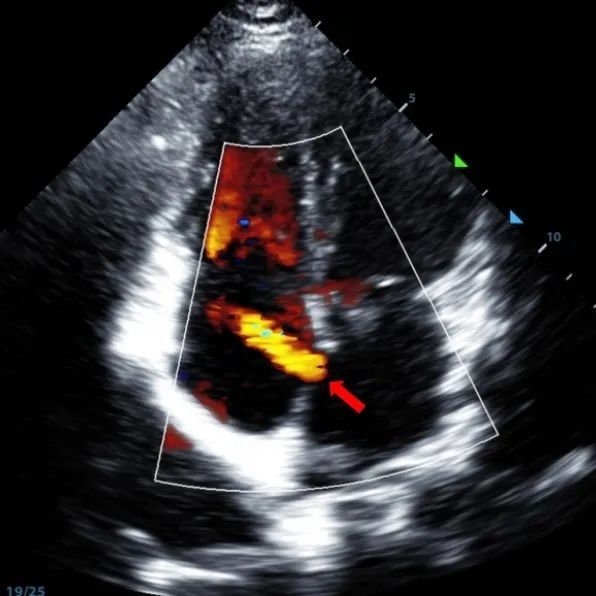

Un garçon de 9 ans avec un TSA secundum (7,5-7,9mm) a été traité à l'aide d'un occulteur MemoSorb BDASD-I 12mm et d'un système d'administration 12F. Aucune complication ou comorbidités n'a été notée avant l'intervention.

Serial echocardiographic follow-ups showed stable device position and favorable cardiac remodeling. Gradual degradation confirmed the occluder's long-term safety and efficacy.